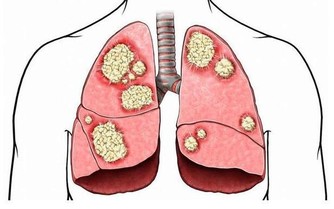

酒精進入人體後,需在肝臟進行“解毒”,其間會生成一種叫乙醛的毒物,對肝臟造成損傷。

乙醛可以被代謝掉,但長期、過量飲酒,就可能引起肝臟的損傷和炎症,或演變為酒精性脂肪肝。

如果不加以控制,酒精性肝硬化就要登場了,在不久的將來,極有可能發展為肝癌。